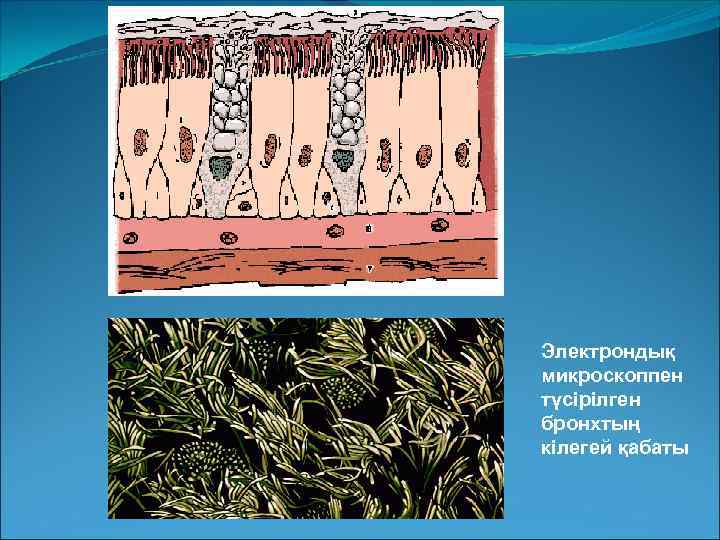

Электрондық микроскоппен түсірілген бронхтың кілегей қабаты